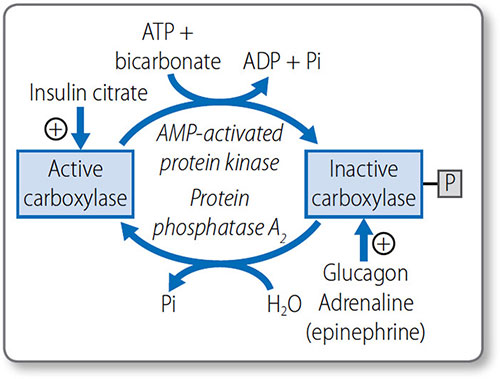

Malonyl coenzyme A synthesis

Some acetyl CoA is carboxylated to form malonyl CoA in an irreversible two-step reaction that requires bicarbonate, biotin and ATP. It is a commitment step in fatty acid synthesis, as malonyl CoA is only involved in fatty acid synthesis.

Both steps are catalyzed by acetyl CoA carboxylase:

- Acetyl CoA is converted to carboxybiotin; one ATP is used

- The carboxyl group is transferred from the biotin to the acetyl CoA to form malonyl CoA.

This is the key regulatory step for fatty acid synthesis (see page 74). The ‘extra’ carbon of malonyl CoA is what allows lipogenesis to be thermodynamically possible.

Fatty acid metabolism is predominately regulated by hormones that affect acetyl CoA carboxylase activity (Figure 1.43):

- When energy is required, adrenaline (epinephrine) and glucagon inactivate it via phosphorylation by AMP protein kinase

- When energy is not required, insulin activates it via dephosphorylation by phosphatase 2A.

Acetyl CoA carboxylase is also activated by citrate and inhibited by AMP and palmitoyl CoA.

Figure 1.43: Regulation of acetyl coenzyme A carboxylase activity. +, activates; P, phosphate; Pi, inorganic phosphate.